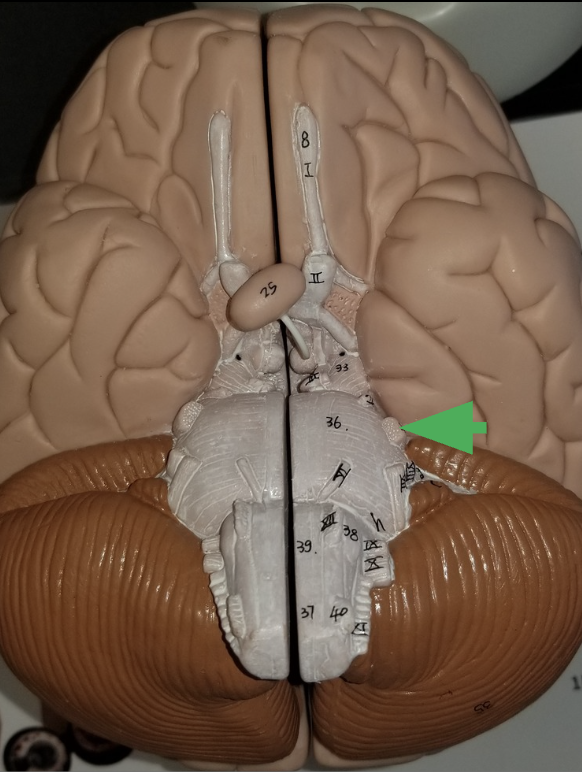

What is the arrow indicating?

1 of the 2 cerebral hemispheres